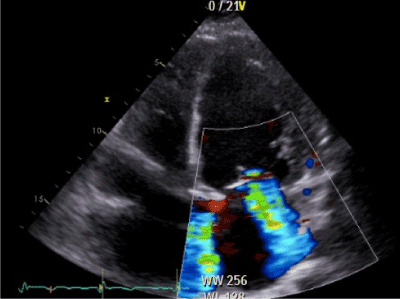

The patient had a Body Mass Index (BMI) of 20, 3 kg/m2. On clinical examination, bilateral basal crepitations of the lung were noticed. In the electocardiogramm, a normofrequent atrial fibrillation was recorded. The chest X-ray showed a cardiomegaly (Figure 1). The patient had normal kidney function and haemoglobin. The initial NT-proBNP measured 2737 pg/ml (normal < 125 pg/ml). The transthoracic two-dimensional echocardiography revealed a highly reduced pump function with an ejection fraction of 18% and a mitral- and tricuspidal regurgitation grade III (Figure 2).

Figure 2.Transthoracic echocardiography : Apical four chamber view  showing  a functional mitral regurgitation (fMR) grade III